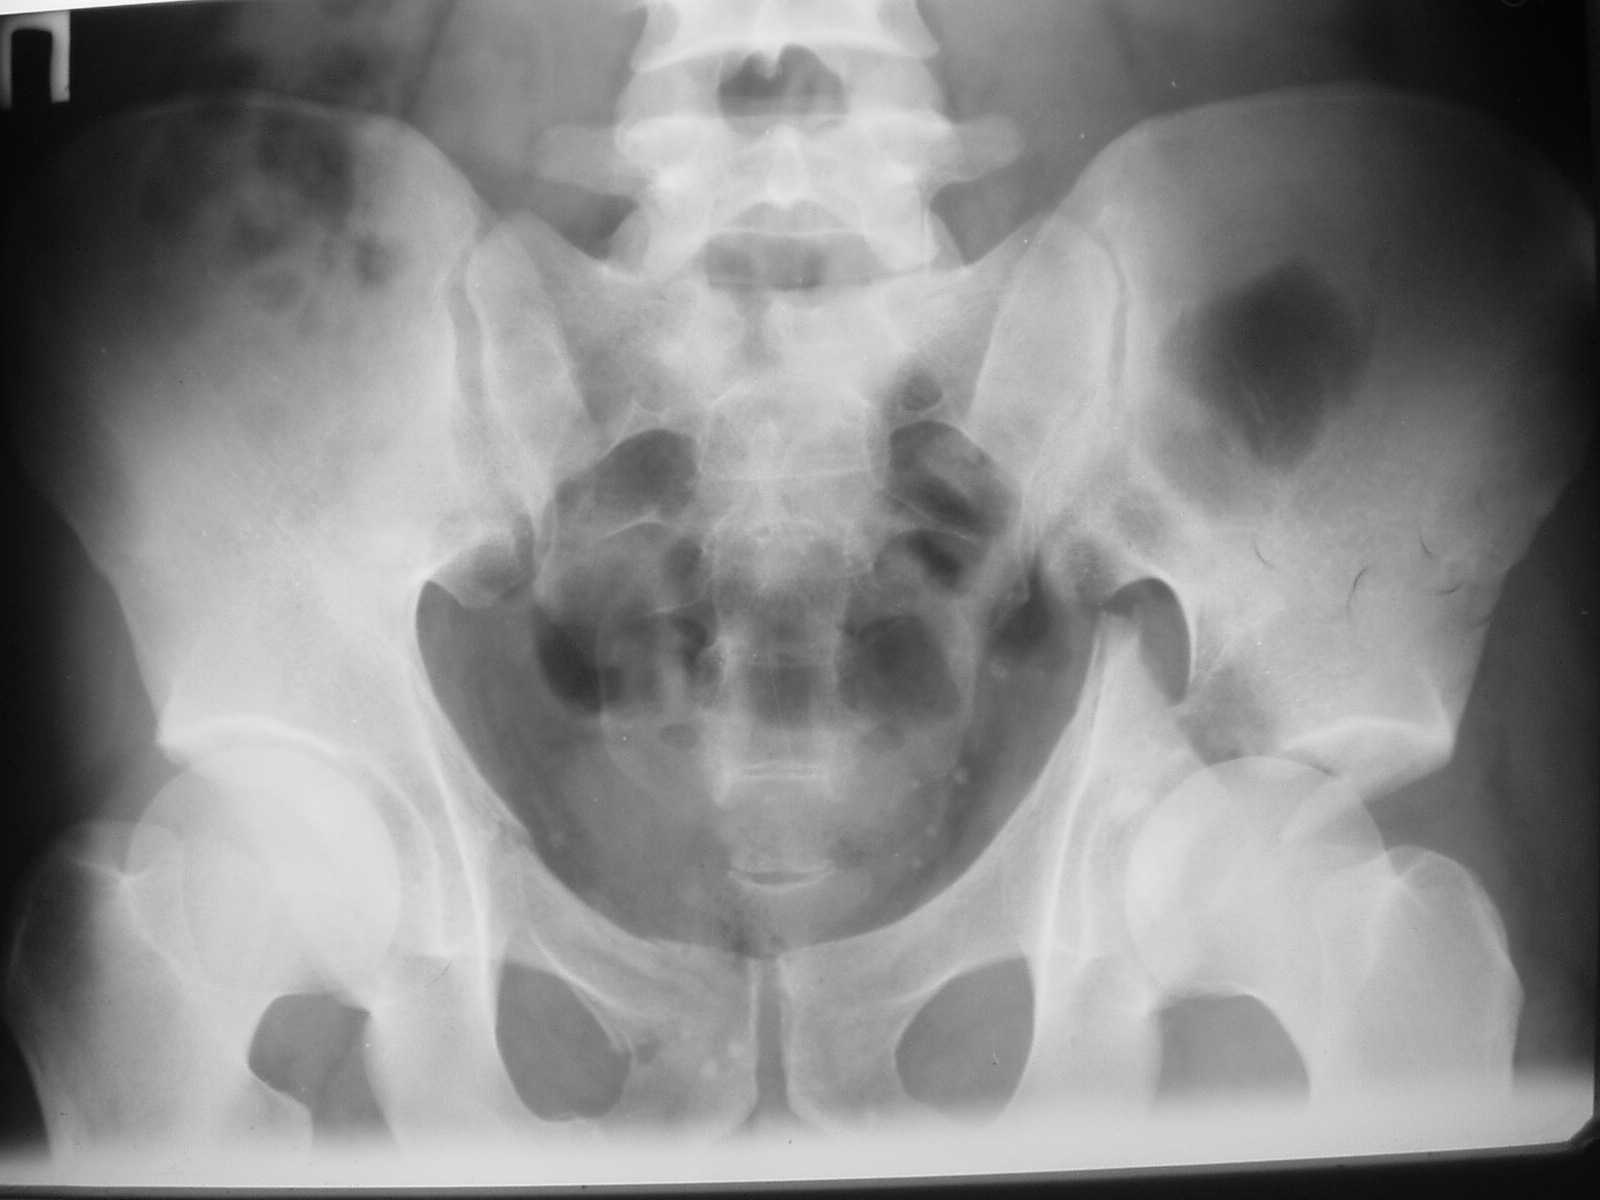

The details of the fracture are not so clear from the images sent...would you be able to send along an AP and Judet images as well as some additional axial images above and below the joint?

I’m not so sure that your patient has a Tr+PW pattern based on the images sent...maybe the fracture’s exact name won’t matter in the long run, but it’d be great to see enough images to make an accurate comment.

Without complete CT images and/or oblique radiographs, it's difficult to answer your question definitively, but it appears that there may not be a posterior wall fracture that requires a posterior approach. A successful reduction through an ilio-inguinal approach will have a faster recovery, and not risk SGN injury or heterotopic ossification.

Here are some more axial images. What is your opinion as for the timing of the operative treatment?